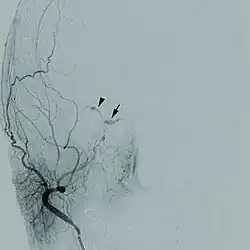

| Cerebral angiogram of a carotid-cavernous fistula | |